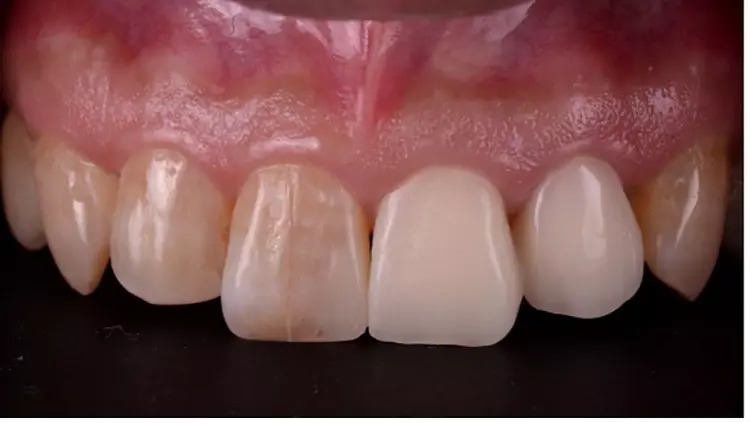

Der 56-jährige Patient stellte sich mit einer dezementierten Krone an Zahn 22 und insuffizientem Zahnersatz an Zahn 21 vor. Die koronale Leakage bestand schon mehrere Tage, bevor der Patient die Praxis aufsuchte. Die Ausgangssituation zeigte, dass beide Zähne zuvor wurzelkanalbehandelt waren (Abb. 1). Nach eingehender Röntgendiagnostik wurde entschieden, die defekte Krone an Zahn 21 zu entfernen und zunächst ein adäquates Kariesmanagement zu betreiben (Abb. 2).